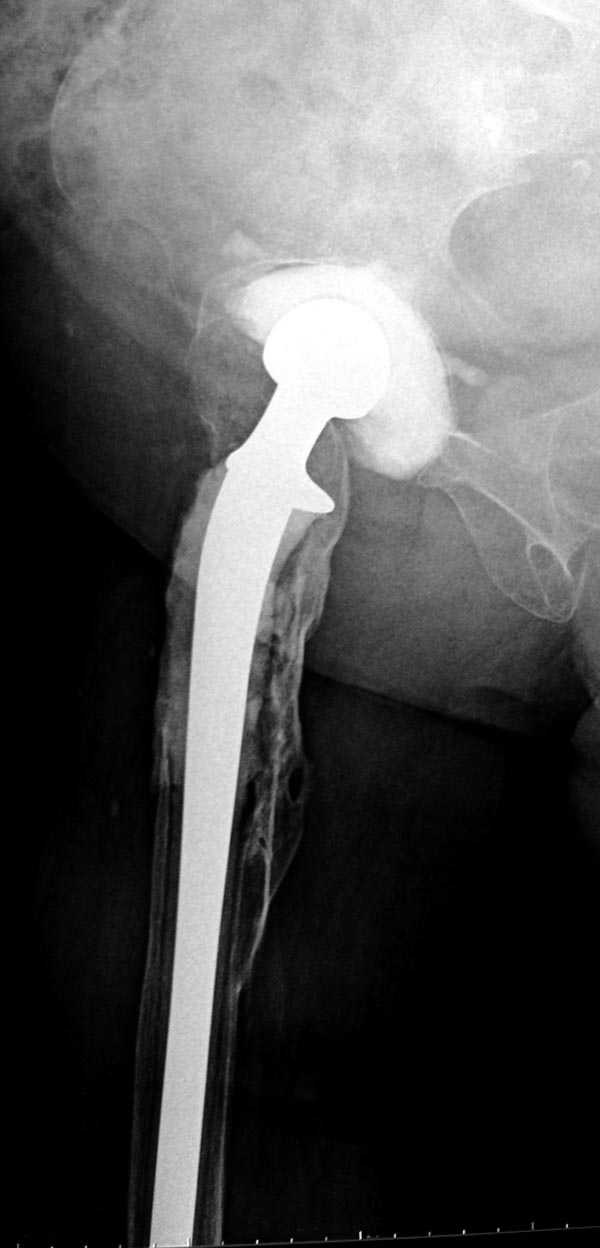

Для бедренного компонента можно применить старую

длинную ножку протеза и желательно малого диаметра.

Цементная смесь наносится вручную на металл и

затем доводится до ровного диаметра поверхности

снятием лишнего цемента шаблоном. Такие шаблоны были в старом интрамедуллярном наборе, различные по диаметру отверстия на металлической пластине. Протез с цементом проводится через отверстие в шаблоне для точного совпадения с размером проксимального римера. Таким образом приготовленный феморальный компонент будет

держаться в бедренной кости плотно.